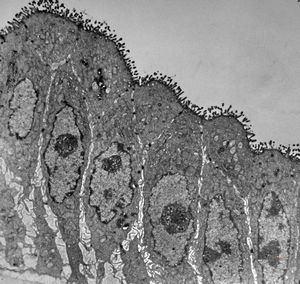

normal jejunal enterocyte

enterocyte - normal and celiacal microvilli